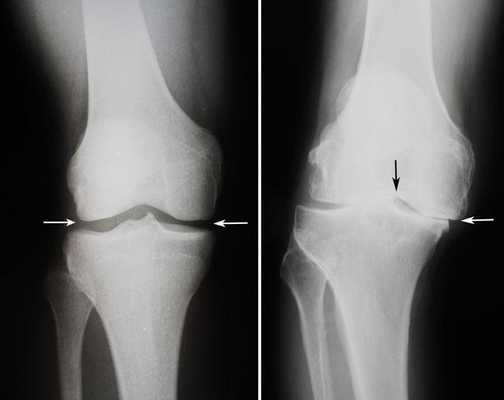

Артроз коленного сустава на рентгене.

Посмотрите на рентген, на нем вы видите, до какой степени при запущенном гонартрозе изношен гиалиновый хрящ, обеспечивающий гладкое скольжение суставных поверхностей. Концевые участки костей грубо деформируются нарушая функции сгибания и разгибания конечности вызывая интенсивный болевой синдром.

Сравнение здорового и пораженного сустава.